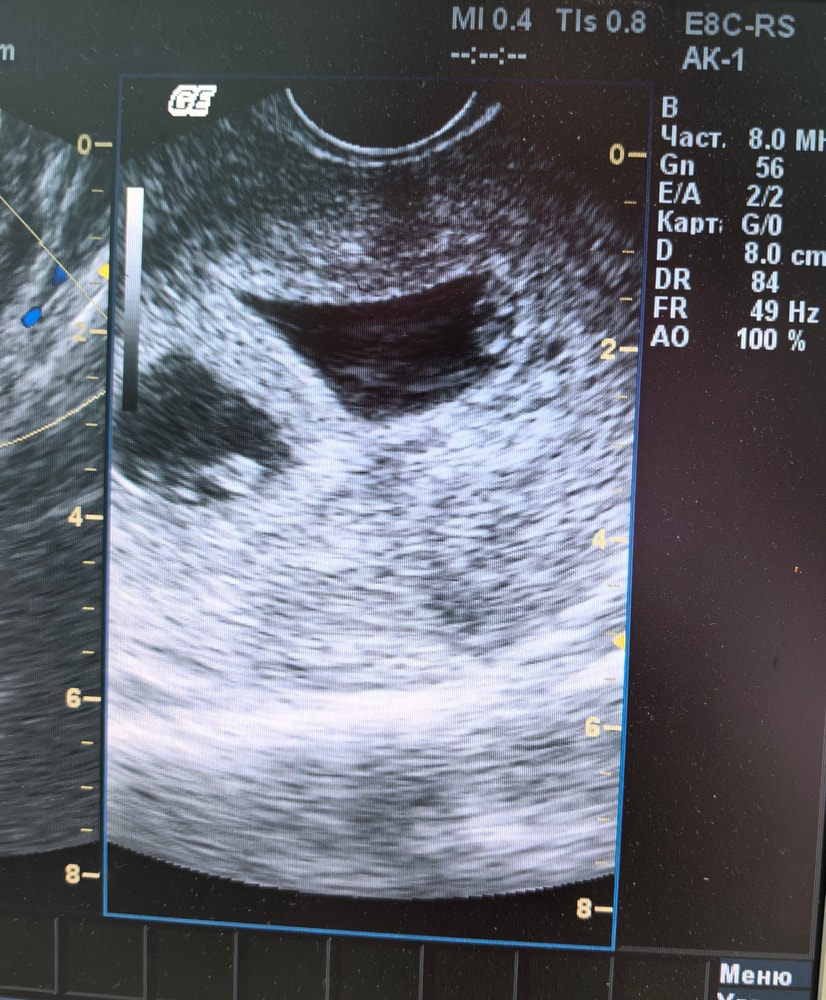

На сроке 6,3 н было первое узи, там мы узнаем, что ждем двойню. Врач описывает два плодных яйца, два жёлтых тела в левом яичнике, что говорит о двух овуляциях, один хорион по передней стенке, второй по задней. Я для себя понимаю, что это ди ди двойня.

Потом я попадаю на сохранение с мазней, делают несколько раз узи, но на руки не выдают заключение. На последнем узи на сроке 8,1 н врач дал заключение узи, но там только ктр малышей и написано, что диамнотическая монохориальная двойня.

Екатерина, да) на фото явно ди ди) королевская двойня вполне может быть))) я когда узнала о своей многоплодной беременности, наоборот хотела одного пола) тогда еще не понимала что при моно ди (мой случай) только так и бывает.